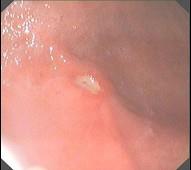

问题 男,34岁,4年来常出现右上腹痛,午夜尤甚,疼痛放射至背部,先后曾发生4次上消化道大出血,,体检仅右上腹压痛。胃镜如图。以下最有可能的是 ( )

选项 A.胃癌 B.慢性胃炎 C.十二指肠球后溃疡 D.胃溃疡 E.胃粘膜脱垂

答案 D